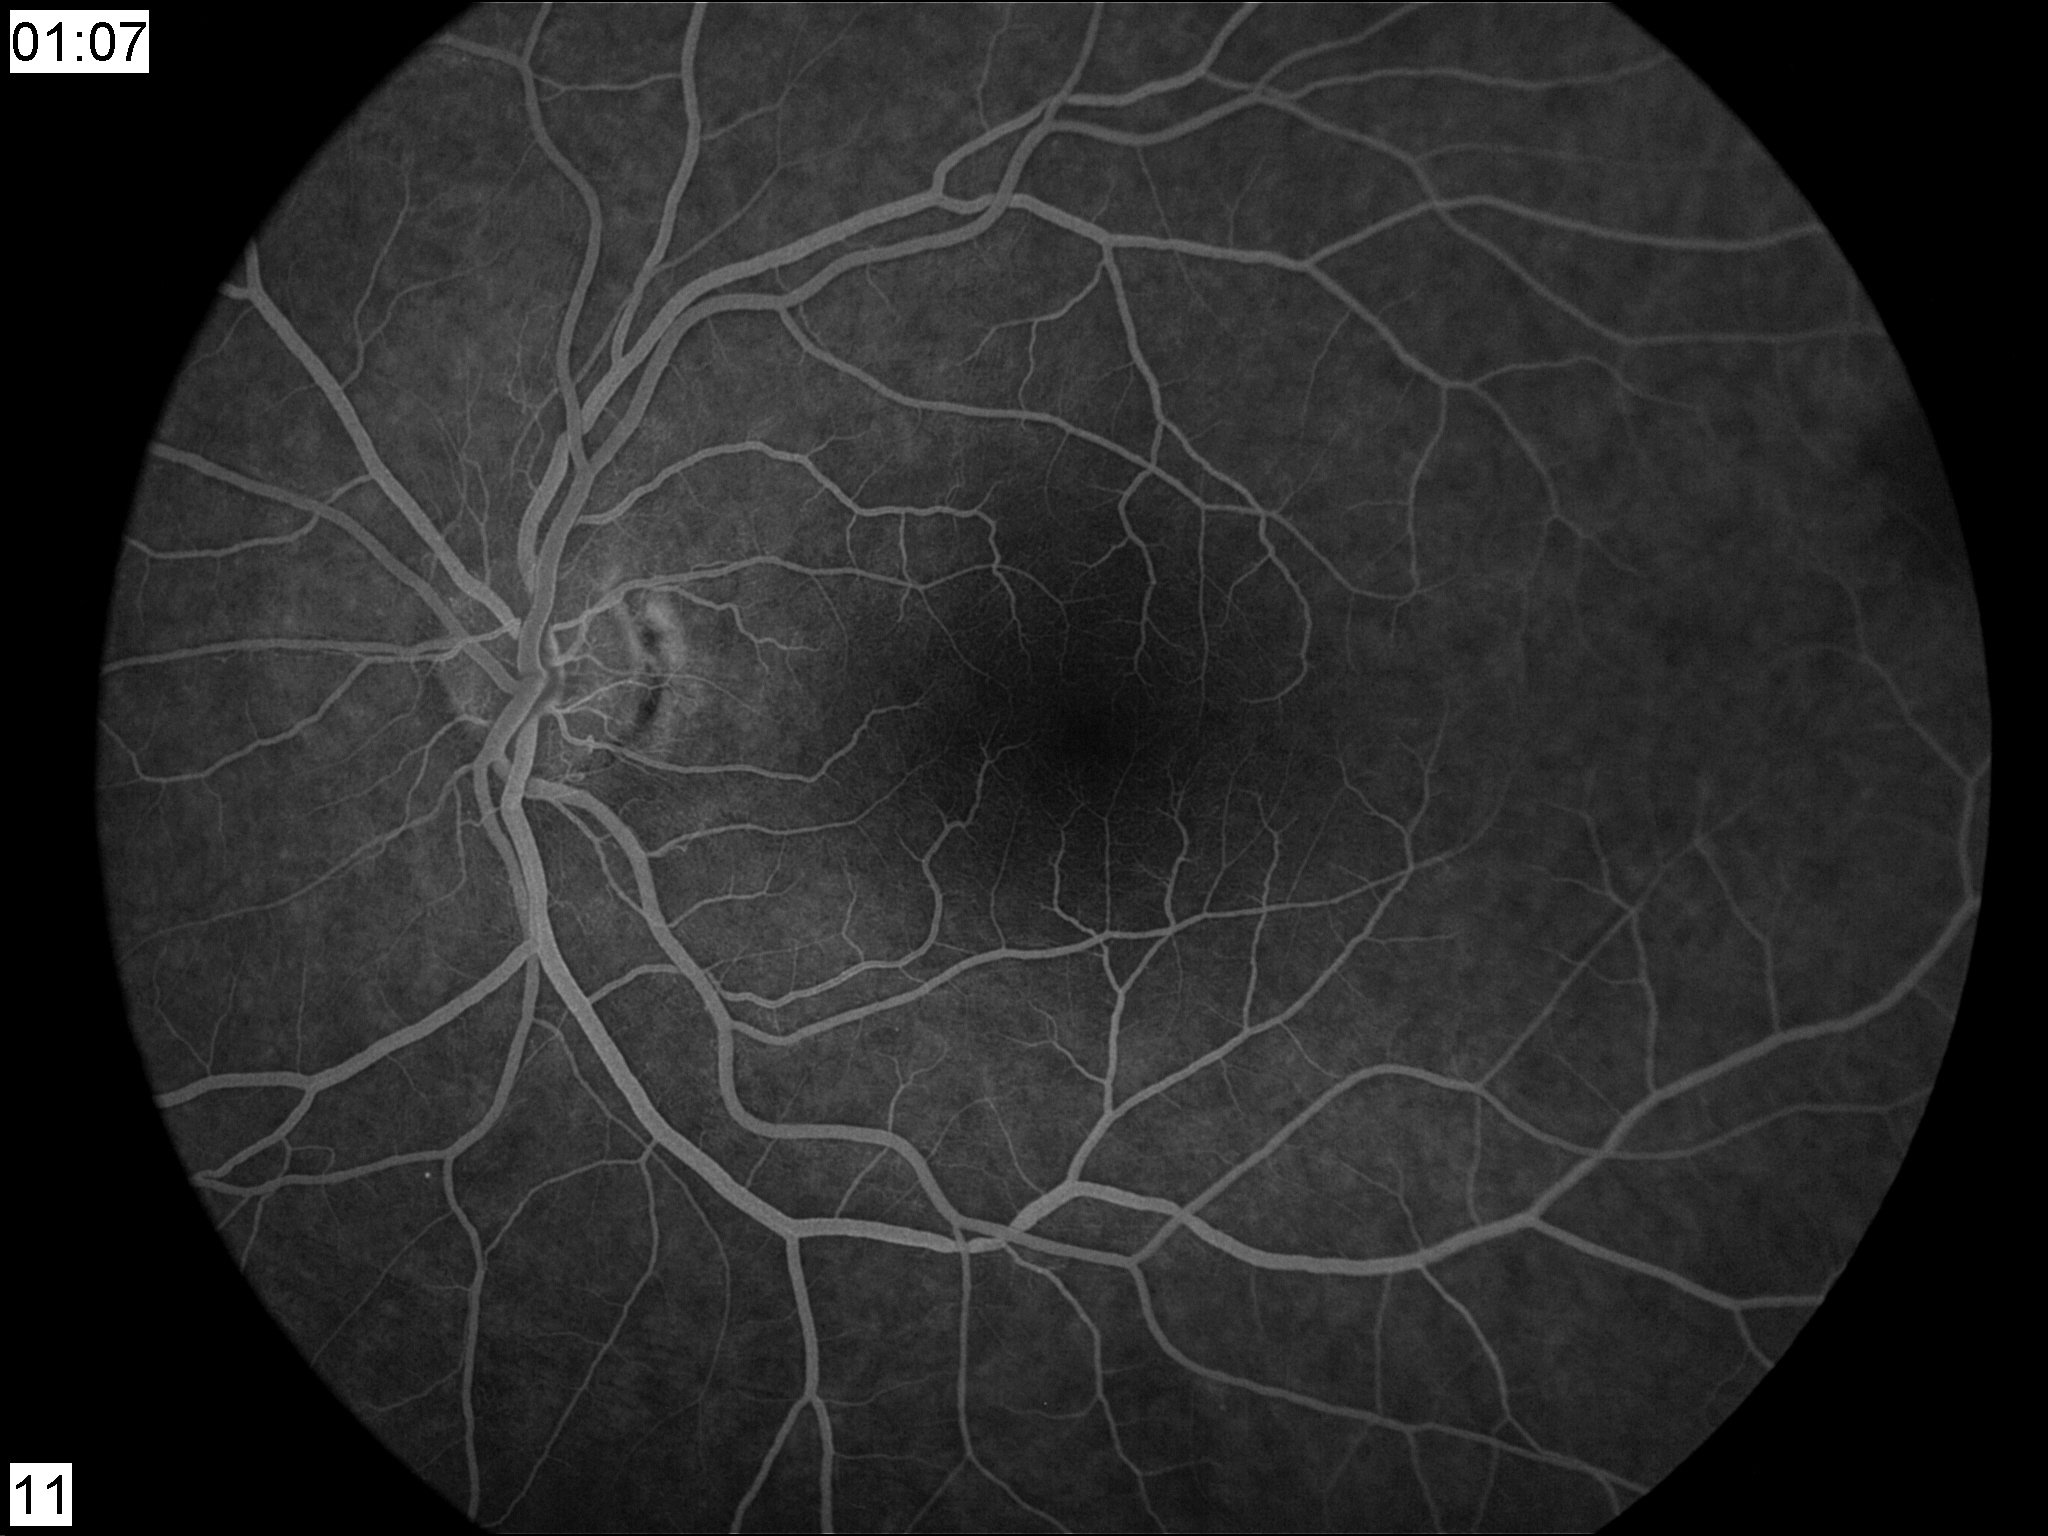

Φλουοροαγγειογραφία ή Angio-OCT: σε υποψία ισχαιμίας ή ανάπτυξης παθολογικών νέων αγγείων.